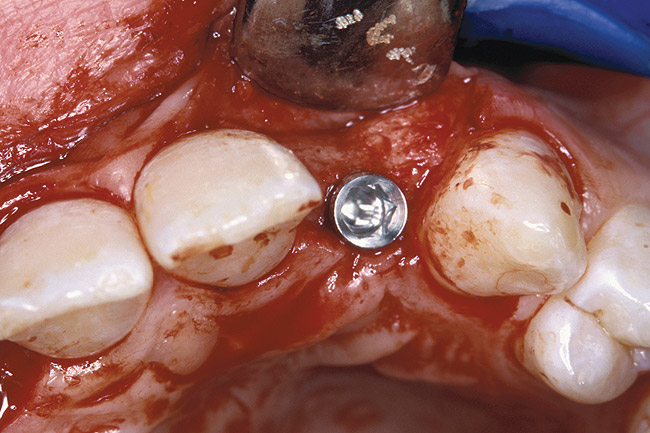

Before the day of surgery, the patient was seen by the orthodontist for the removal of the orthodontic brackets. The patient still was not pleased with the position of the two centrals, and it was determined that this would be addressed after implant placement (Figure 26). The anatomical variations of the crestal tissue and lack of interdental papilla can be appreciated in the close-up views of the right and left sites (Figure 27 and Figure 28). There were no surprises on the day of surgery as all of the decisions were made during the planning phase, before the scalpel ever touched the patient. The occlusal view of the CT 3D model revealed the wider alveolar ridge on the right side and thinner crest on the left side (Figure 29). This was confirmed when the full-thickness mucoperiosteal flaps were elevated, and the underlying bone revealed (Figure 30). The tooth-borne templates were designed to facilitate the drills and drilling sequence specific to the diameters of the predetermined implants (Figure 31). Each template contained an embedded 5-mm long stainless steel tube, which was approximately 0.2-mm wider than each drill (just wide enough to allow for the drills to rotate freely). Once positioned over the natural teeth, the template was secure and offered precision accuracy in transferring the implant locations from the original software-designed plan, allowing the potential for internal and external irrigation (Figure 32).

The 3.7-mm diameter Tapered Screw-Vent implant drilling sequence requires three drills: pilot, intermediate, and final sizing. Thus, three separate templates were fabricated to accommodate these sizes. The templates were removed easily and replaced with the next sequential size in less time than it takes to change the drill on the surgical handpiece. After the osteotomies had been completed, the implants were delivered to the site (Figure 33 and Figure 34). For this internal hex connection implant, the author recommends that the flat of the anti-rotational hex be positioned to the facial for proper orientation of the restorative components (Figure 35). Pre-prepared margins were created from a milled titanium fixture mount transfer post, which was delivered to the implant as support for an immediate transitional restoration. The facial “dot” helped to confirm the orientation of the abutment to the facially positioned flat side of the internal hex connection (Figure 36). Before cementation of the transitional acrylic restorations, a closed-tray, fixture-level impression was made, and a soft-tissue model was fabricated.

Figure 30  VIRTUAL PLANNING AND SURGERY The information gained from the 3D model was confirmed when the flaps were elevated.

Figure 30

Figure 32  VIRTUAL PLANNING AND SURGERY A surgical template was derived from the final treatment plan created in the software, which facilitated the drilling sequence and precise location of placement.

Figure 32